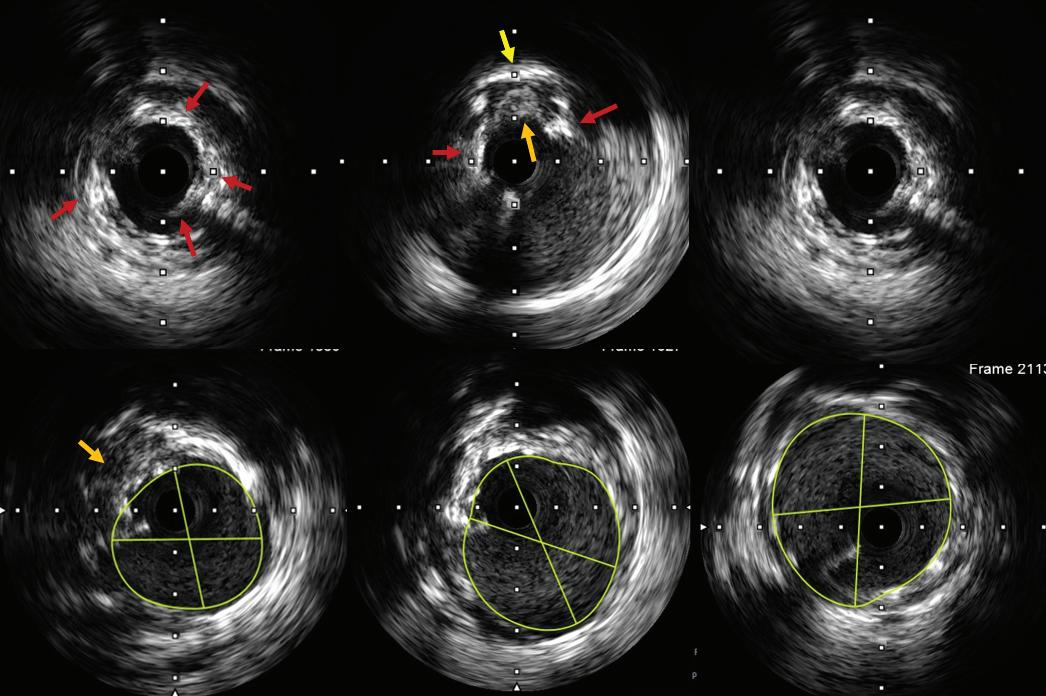

Hs-cTnT 12–52 ng/l and delta 3 to <5 ng/l at 1–3 h

Hs-cTnT >sex-specific 99th percentile or high risk score and 2–3 h delta >RCV

Hs-cTnT <sex-specific 99th percentile and low risk score

Not applicable

0/1 and 0/3 h 0/1, 0/2 and 0/3 h 0/2 and 0/3 h

Recommends the use of HEART risk score

Recommends the use of GRACE risk score models for estimating prognosis

Requires the use of HEART score for final disposition

Hs-cTn used Hs-cTnT Hs-cTnT and TnI Hs-cTnT and TnI

AMI = acute MI; APSC = Asian Pacific Society of Cardiology; ED = emergency department; ESC = European Society of Cardiology; GRACE = Global Registry of Acute Coronary Events; HEART = History, Electrocardiogram, Age, Risk factors and Troponin; Hs-cTn = high-sensitivity cardiac troponin; Hs-cTnT = high-sensitivity cardiac troponin T; RCV = reference change value; Malaysian = Malaysian Expert Consensus Group; TnI = Troponin I.